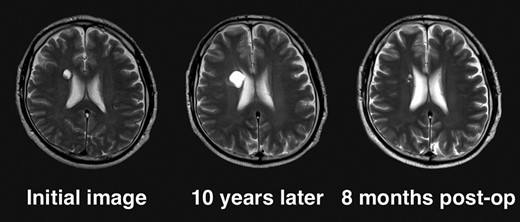

Clinical course of the lesion on follow-up neuroimaging. The tumor increased in size during 10 years of follow-up. No recurrence has been seen as of 8 months postoperatively.

Given the absence of neurological symptoms, the patient was followed conservatively. After a follow-up period of 10 years, the lesion started to increase in size from 10 to 18 mm, accompanied by worsening of headaches. MRI revealed that the increased size of the lesion was attributable to an enlargement of the cystic component and the mural nodule (Fig. 1). A cystic mass with a gadolinium (Gd)-enhancing cyst wall and mural nodule were present. Signal intensity of the cystic component was high on T2-weighted imaging and fluid-attenuated inversion recovery (FLAIR) imaging. The cyst wall and nodule showed low signal intensity on T2*-weighted imaging (Fig. 2). Surgical removal was performed via a trans-cortical approach achieving gross total removal. The cystic component was covered with a transparent thin membrane containing clear yellow fluid, while the mural nodule comprised white, tough tumorous tissue. The lesion showed no invasion into the lateral ventricle. The postoperative course was uneventful, with no complications. No headache and no sign of recurrence have been seen, as of 13 months after surgery (Fig. 2).